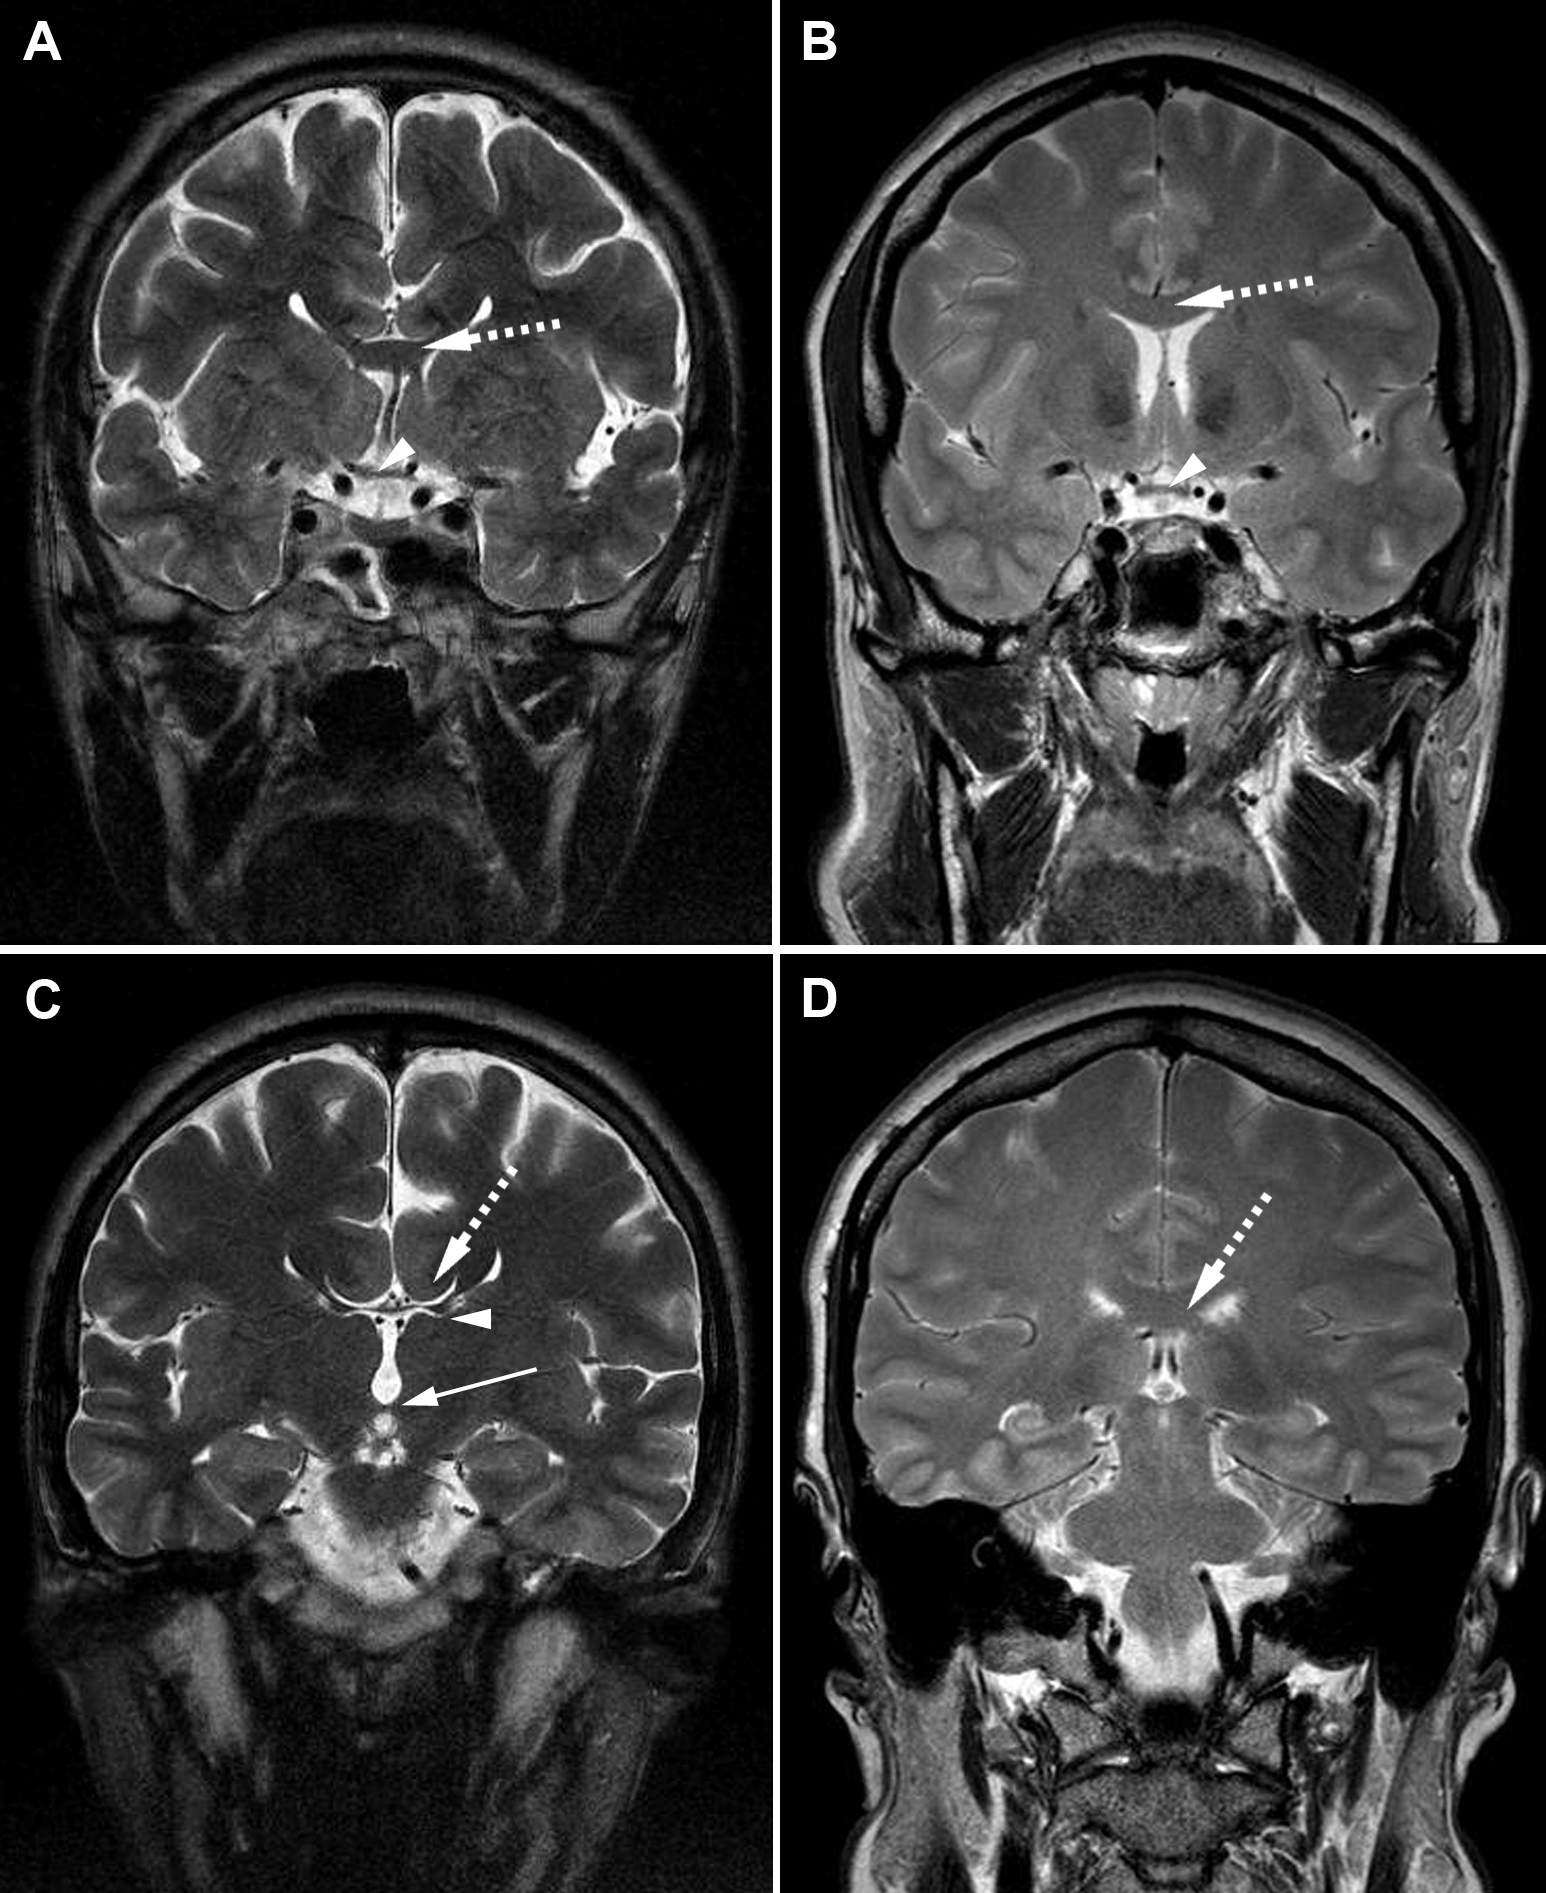

Figure 4. Coronal cerebral T2-weighted

magnetic resonance images. A: Patient I-1 from Family 3. Dashed

arrow shows severe hypogenesis of the corpus callosum with small amount

of remnant tissue localized at the virtual connection between the genu

and the body of the corpus callosum; arrow head shows the atrophic

optic chiasm. B: Normal MRI images. Dashed arrow shows normal

corpus callosum and arrow head shows normal optic chiasm. C:

Patient I-1 from Family 3. Dashed arrow shows lateral callosal bundles

of Probst, which are hemispheric connection fibers that did not cross

the midline and that are seen in callosal dysgenesis. Superomedial

margins of the lateral ventricles are indented by the Probst bundles.

Arrow head shows remnants of the corpus callosum. Lower arrow shows

normal posterior commissure. D: Normal MRI image with dashed

arrow pointing normal corpus callosum.